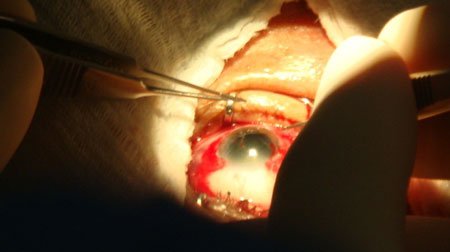

Durante dos días, costeños con problemas avanzados de cataratas y pterigión fueron intervenidos quirúrgicamente por médicos certificados del Colegio de Oftalmología de la Ciudad de Oaxaca.

Al respecto, la Coordinadora Estatal del Programa de Cirugía Extramuros, Liliam Irasema García Pérez, explicó que 36 costeños fueron beneficiados con las intervenciones: 16 de pterigión y 20 de cataratas.